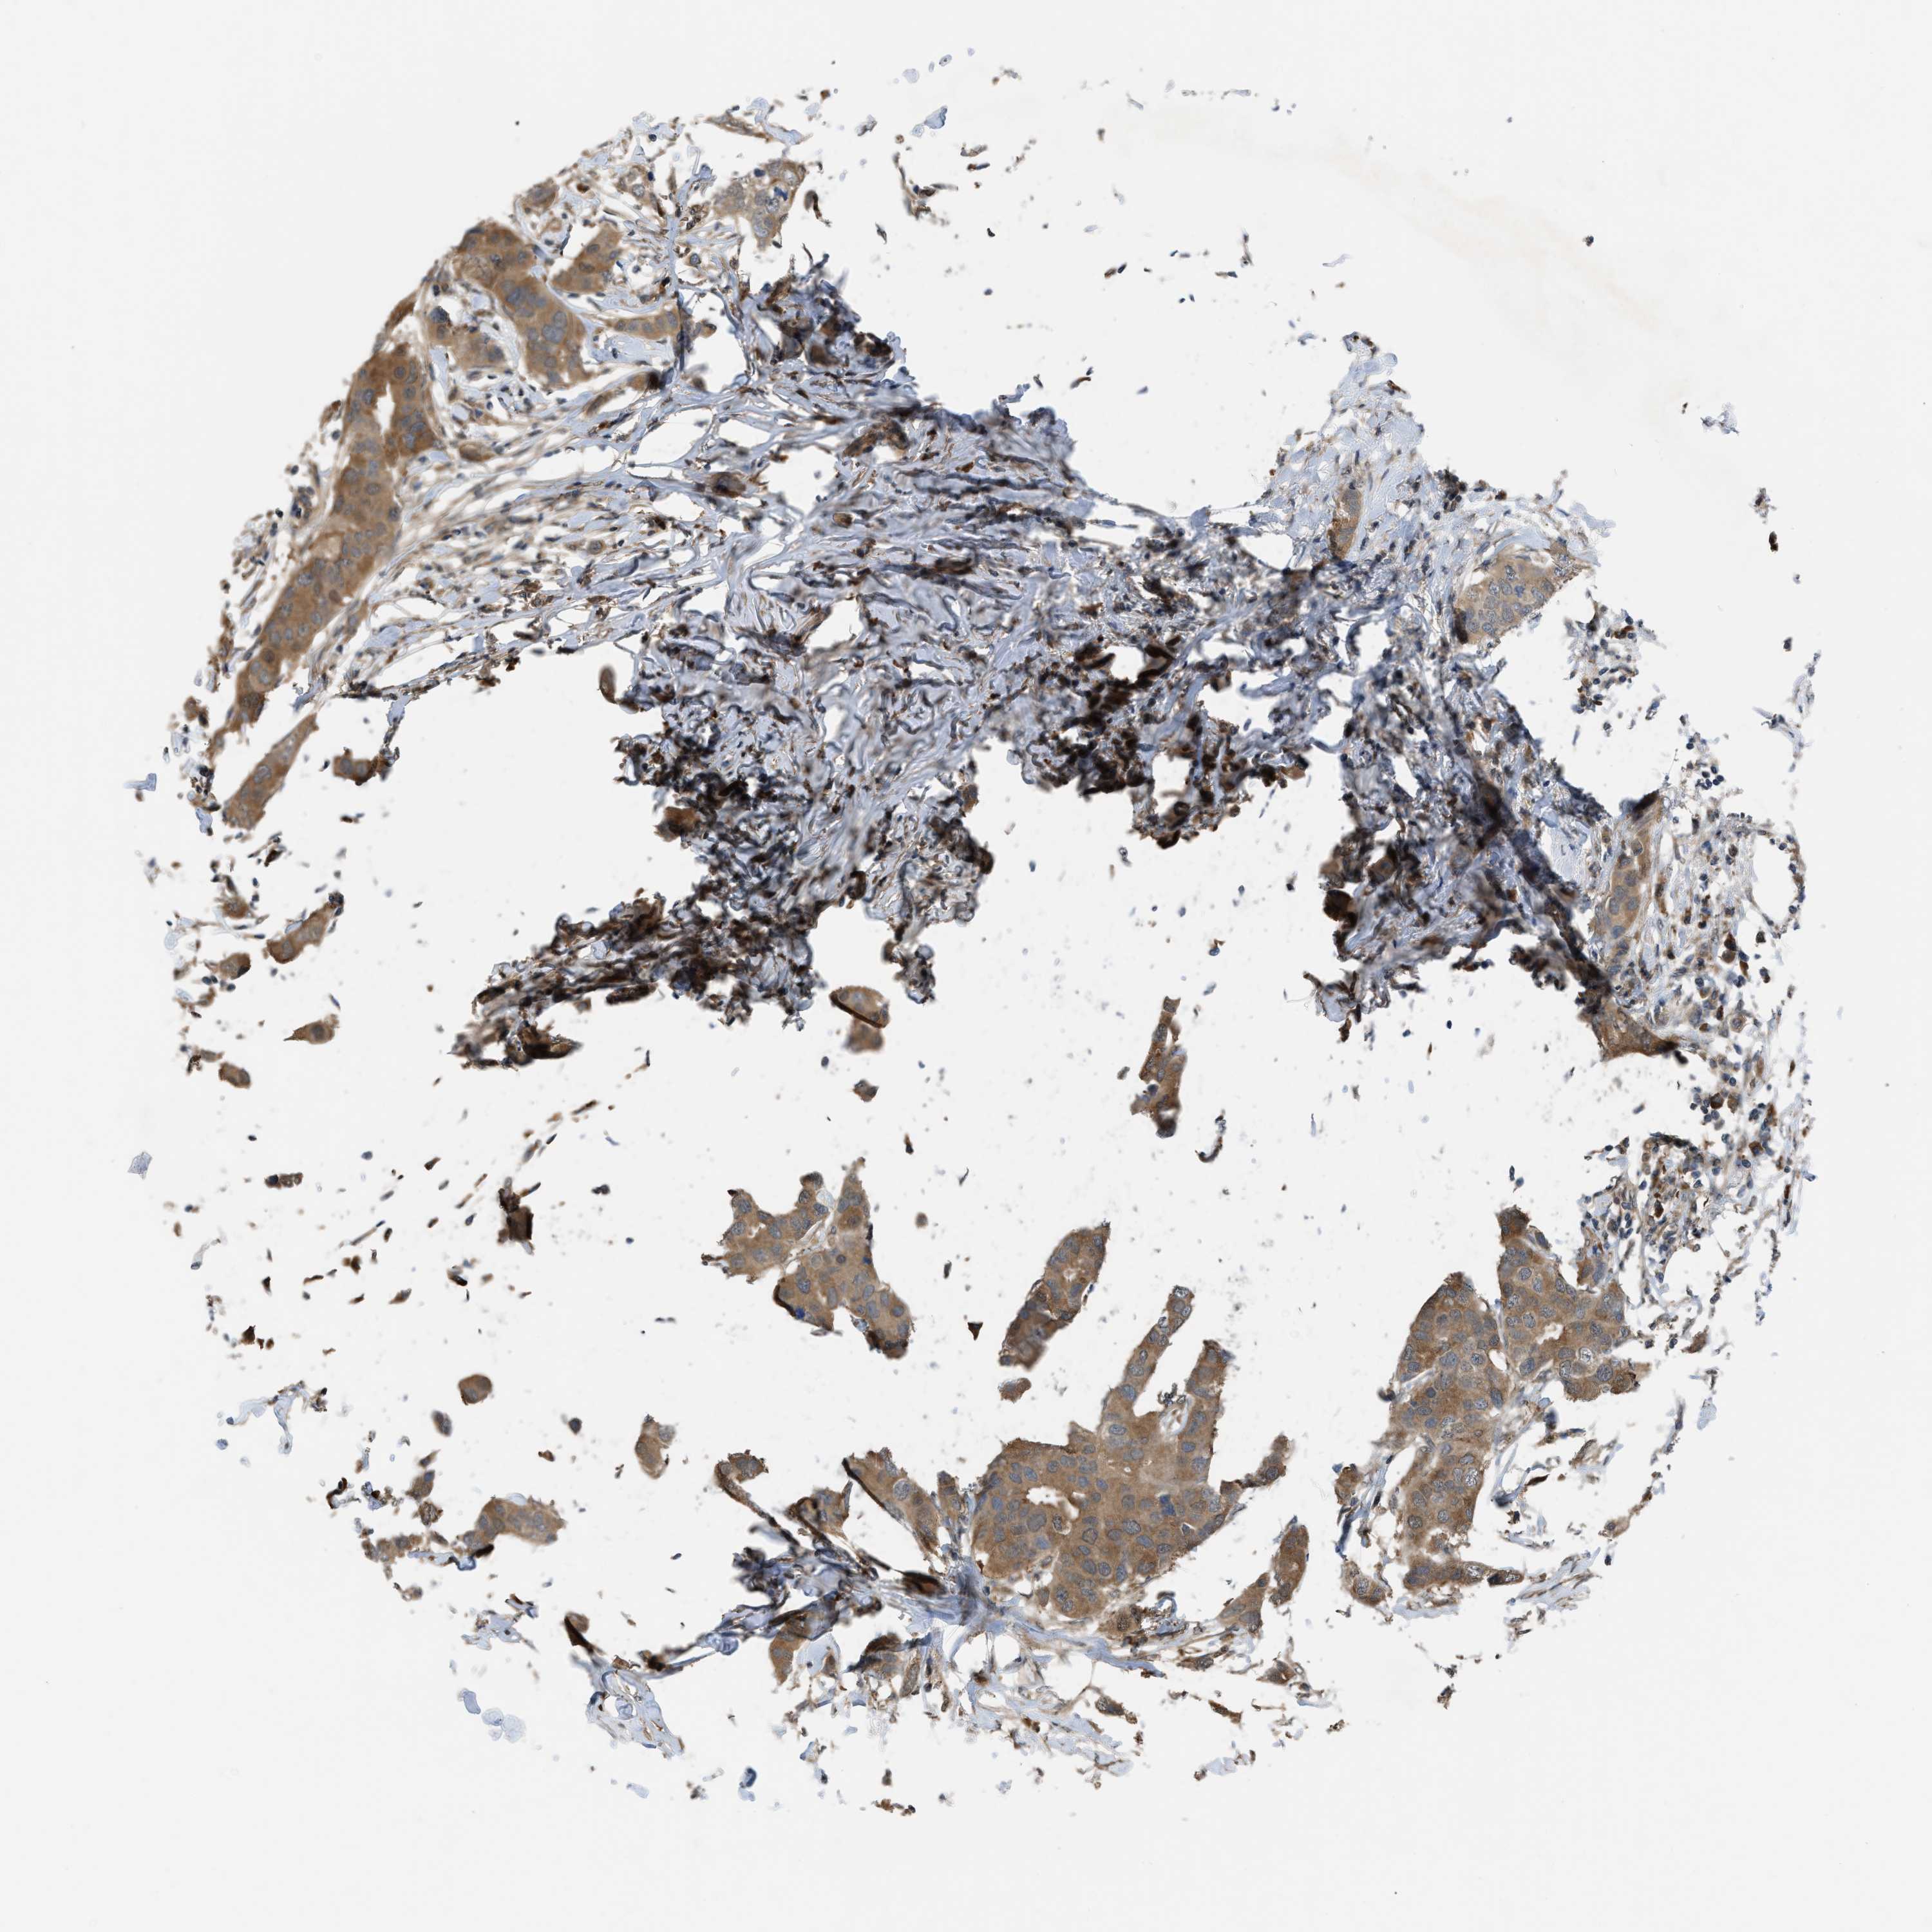

CANCER BREAST CANCER Show tissue menu

BRCA TCGA BRCA VALIDATION PROTEIN EXPRESSION